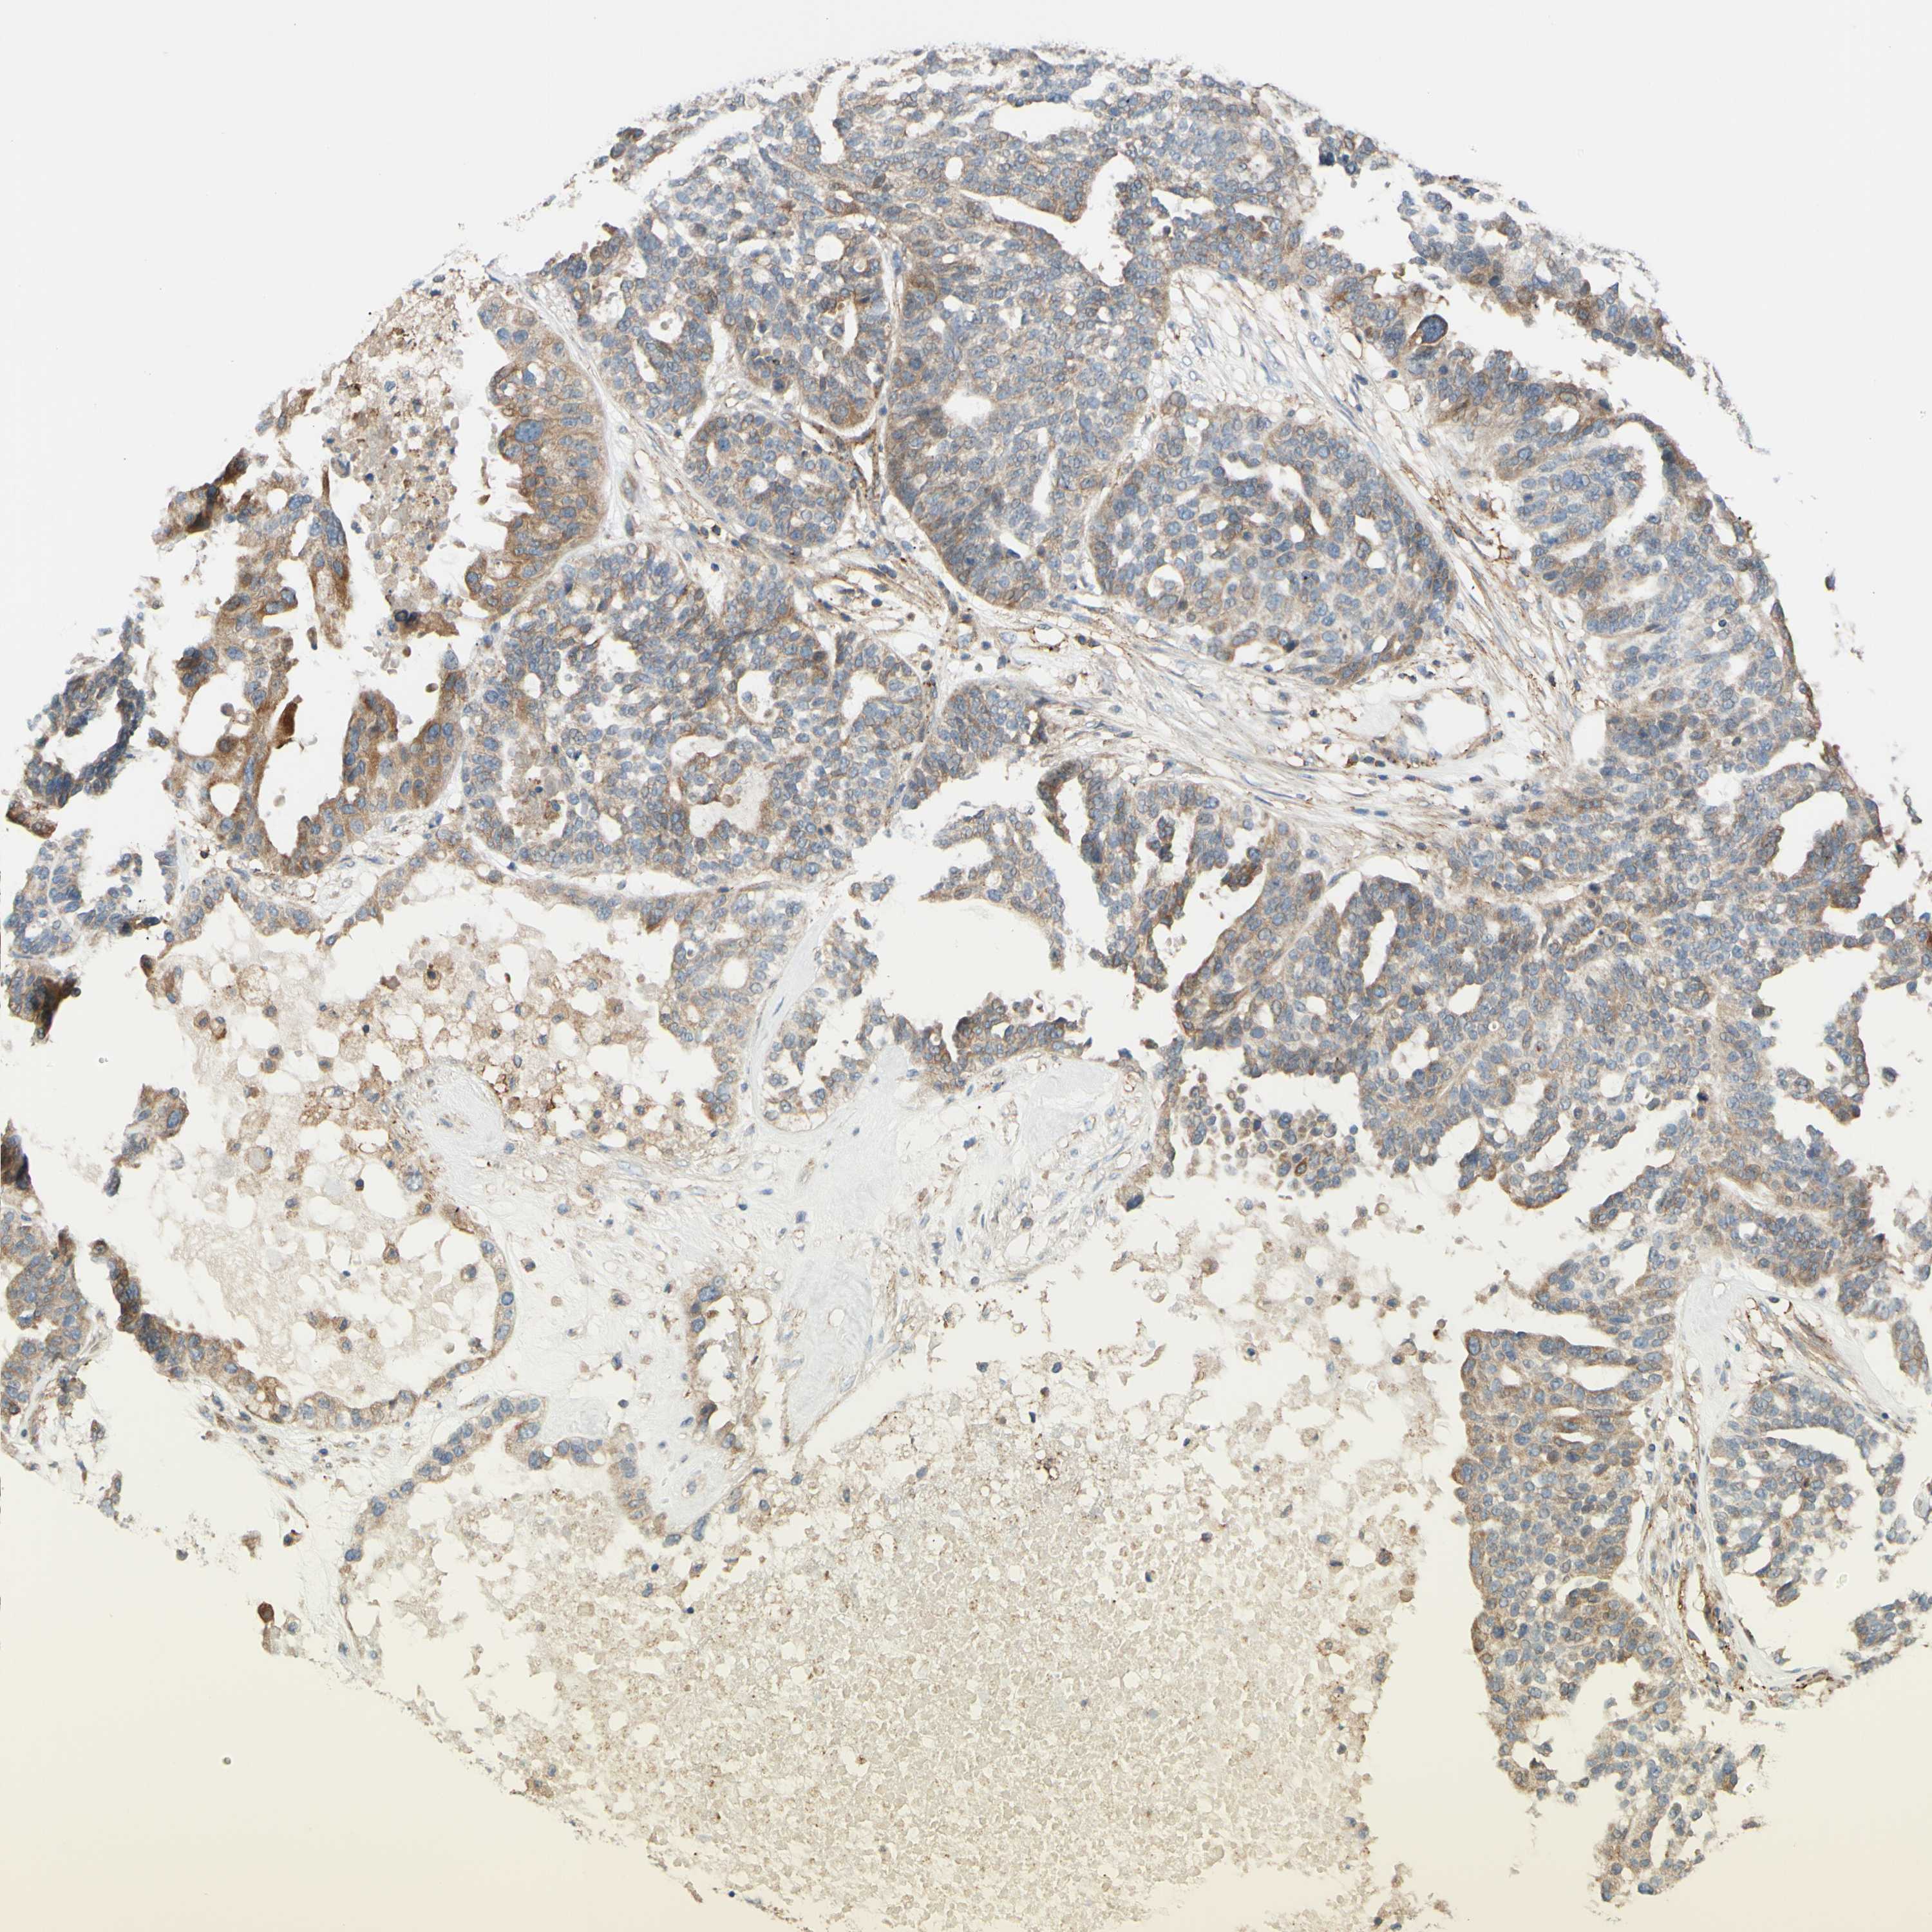

OVARIAN CANCER - Protein expressioni

A mouse-over function shows sample information and annotation data. Click on an image to view it in a full screen mode. Samples can be filtered based on level of antibody staining by selecting one or several of the following categories: high, medium, low and not detected. The assay and annotation is described here.

Note that samples used for immunohistochemistry by the Human Protein Atlas do not correspond to samples in the TCGA dataset.

Antibody stainingi

Antibody staining in the annotated cell types in the current human tissue is reported as not detected, low, medium, or high, based on conventional immunohistochemistry profiling in selected tissues. This score is based on the combination of the staining intensity and fraction of stained cells.

Each image is clickable and will lead to virtual microscopy that enables deeper exploration of all samples and also displays staining intensity scores, fraction scores and subcellular localization as well as patient and tissue information for each sample.

Antibody HPA010136

Antibody CAB004372

Staining

High

Medium

Low

Not detected

Intensity

Strong

Moderate

Weak

Negative

Quantity

>75%

75%-25%

<25%

None

Location

Nuclear

Cytoplasmic/membranous

Cytoplasmic/membranous,nuclear

Cystadenocarcinoma, serous, NOS

Carcinoma, endometroid

Cystadenocarcinoma, mucinous, NOS

Carcinoma, NOS